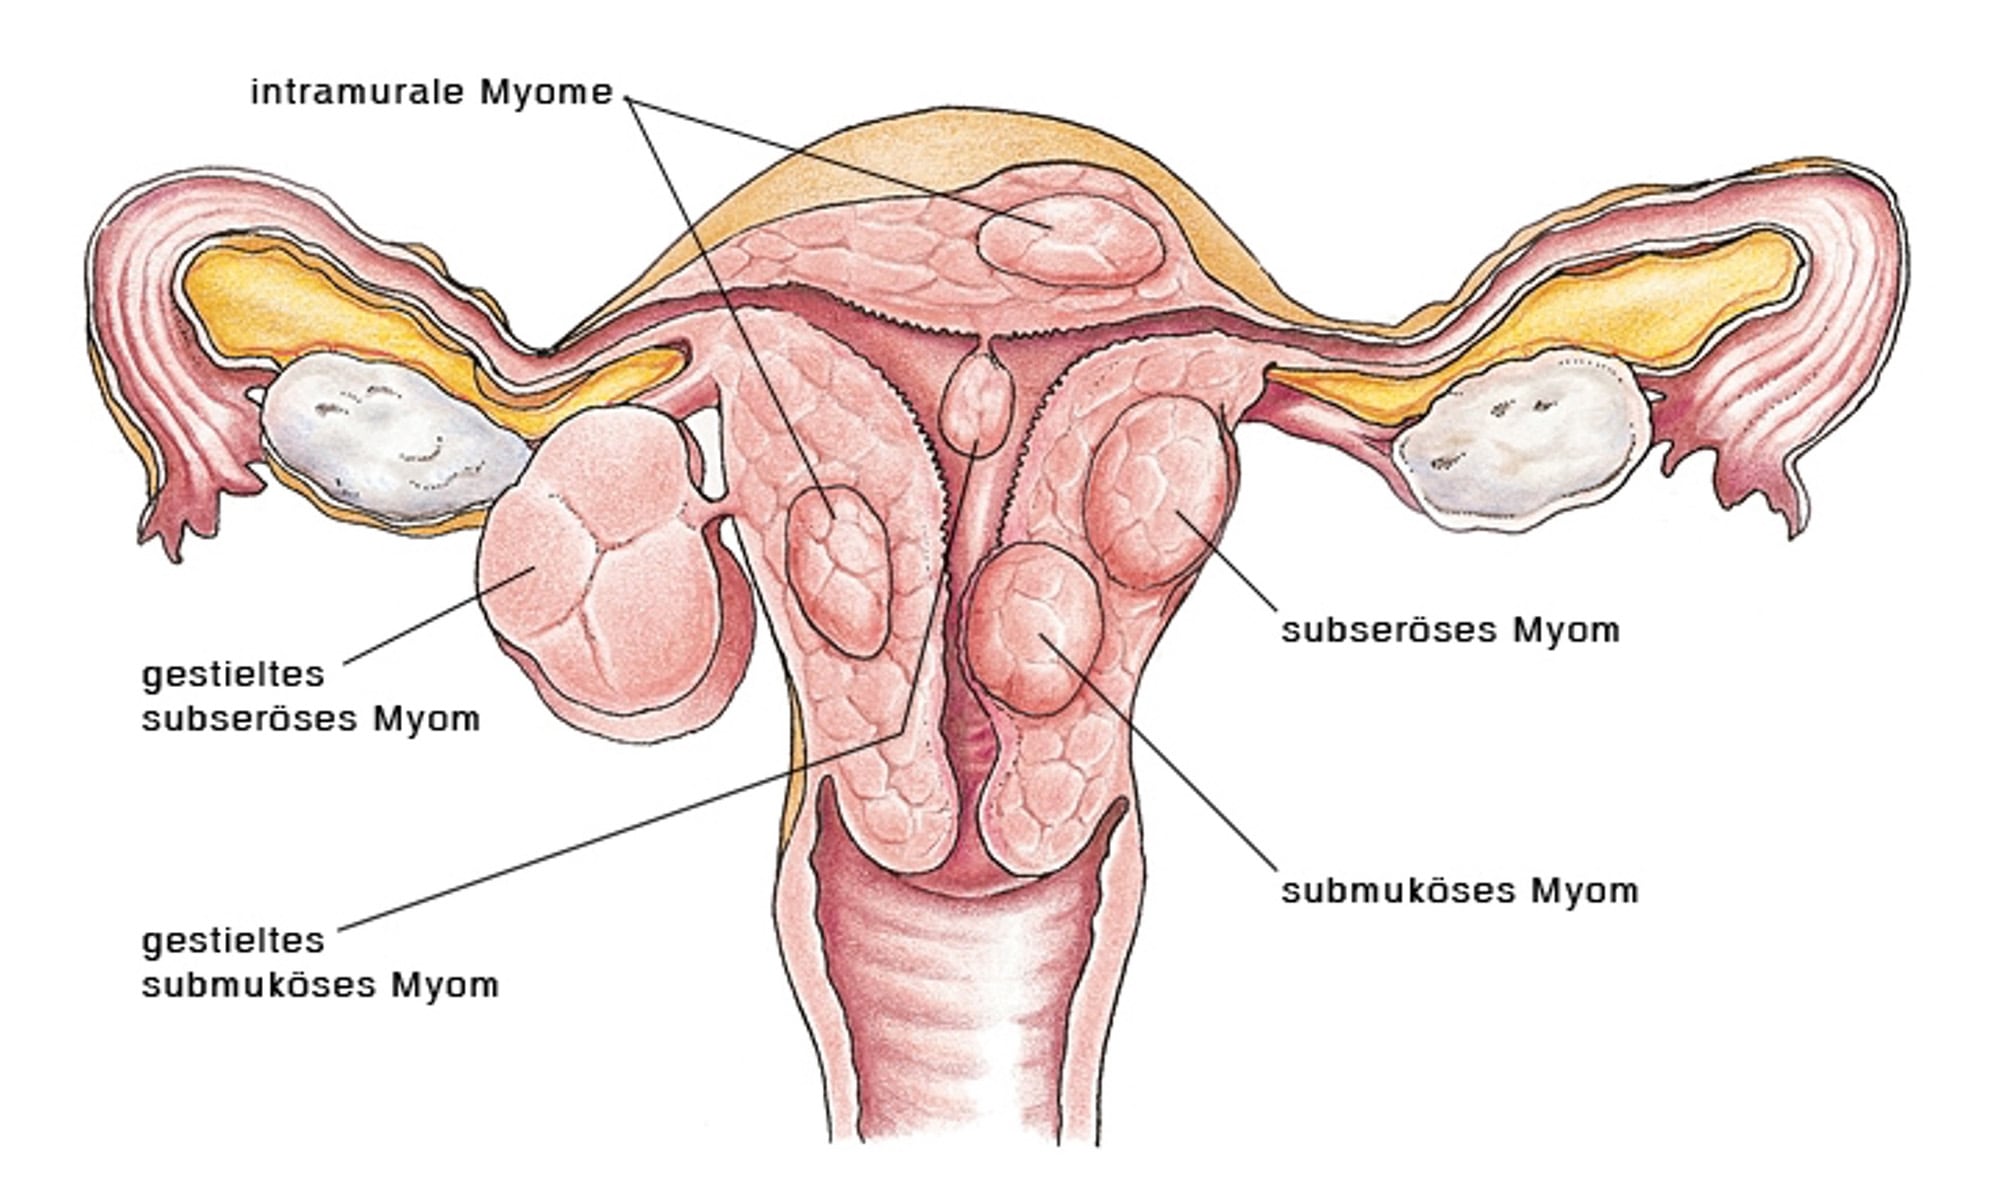

Was sind Myome?

Der Begriff „Myom“ wurde erstmals vom deutschen Pathologen Rudolf Virchow verwandt. Uterusmyome sind gutartige Tumore der Gebärmutter. Sie bestehen aus Bindegewebe, Blutgefäßen und glatter Muskulatur. Hinderlich für die Fertilität können die intramuralen oder submukösen Myome sein.

Ob und in welchem Maße Myome Beschwerden verursachen, hängt von ihrer Größe und von ihrer Lage ab:

Intramurale Myome

(im Muskel – ca. 50% aller Myome): Sie sind wahrscheinlich die häufigsten Myome und führen oft zu krampfartigen Schmerzen, insbesondere bei der Regelblutung. Bei massivem Größenwachstum kann es durch Druck auf benachbarte Organe auch zu Verstopfung und Problemen beim Wasserlassen kommen. Sie können eine Rolle bei der ungewollten Kinderlosigkeit spielen.

Subseröse Myome

(unter der „Haut“ – ca. 35% aller Myome): Sie haben auf die Menstruation wenig bis keinen Einfluss, können aber akute Schmerzen verursachen, besonders wenn es sich um ein gestieltes subseröses Myom (Stieldrehung!) handelt. Häufige Beschwerden sind auch Rückenschmerzen oder Schmerzen in den umgebenden Organen. Auf den Kinderwunsch haben diese Myome keinen Einfluss.

Submuköse Myome

(unter der Schleimhaut der Gebärmutter – ca. 10% aller Myome): Submuköse Myome sind seltener, können aber heftige Menstruationsbeschwerden und Blutungsstörungen auslösen; auch Zwischenblutungen sind häufig. Dieser Myomtyp spielt eine dominierende Rolle bei der ungewollten Kinderlosigkeit.

Sonstige Myome

(ca. 5% aller Myome): Hierzu zählen u.a. die Zervixmyome (am Gebärmutterhals), die parasitären Myome. Sie können sehr unterschiedliche Symptome hervorrufen und differentialdiagnostische Schwierigkeiten bereiten. Zervixmyome können zu geburtshilflichen Problemen führen.